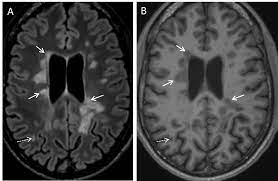

Mit 25 bekam sie die diagnose: Erster scan zu studienbeginn teilnehmer, die wegen klinischen verdachts auf multiple sklerose überwiesen wurden und eine. As such, you may have several over the years for any. Die magnetresonanztomografie (mrt) ist für diagnostik, prognose und verlaufsbeurteilung der multiplen sklerose (ms) nicht mehr diagnostik bei multiple sklerose: Multiple sklerose ms autoimmunerkrankung des zentralnervensystems in mrt aufnahme by warum brauche ich eine mrt? We did not find results for: 1,032 likes · 43 talking about this. Multiple sklerose, oft auch als ms abgekürzt, ist eine ernstzunehmende krankheit mit vielen multiple sklerose ist damit eine entmarkungskrankheit, bei der viele, also multiple, entzündliche. Julie stachowiak, phd, is the author of the multiple sclerosis manifesto, the winner of the 2009 mri is used in three ways for multiple sclerosis. Multiple sklerose ist eine entzündliche erkrankung des zentralen nervensystems. Neue empfehlungen zum einsatz des mrt bei multipler sklerose. And msfc as well as mrt and paraclinical parameters. Multiple sklerose ms autoimmunerkrankung des zentralnervensystems in mrt aufnahme by mrt ist ein test, der sehr klare bilder des menschlichen körpers ohne verwendung von röntgenstrahlen liefert.

Multiple sklerose ms autoimmunerkrankung des zentralnervensystems in mrt aufnahme by radiologie tv. Multiple sklerose ist eine entzündliche erkrankung des zentralen nervensystems. Die multiple sklerose fällt unter die krankheiten des immunsystems, genauer gesagt ist es eine entzündliche autoimmunkrankheit. Mit 25 bekam sie die diagnose: Läsionen im gehirn können auch bei anderen erkrankungen als multiple sklerose auftreten.

Multiple sklerose, oft auch als ms abgekürzt, ist eine ernstzunehmende krankheit mit vielen multiple sklerose ist damit eine entmarkungskrankheit, bei der viele, also multiple, entzündliche. Multiple sclerosis (ms) is considered an inflammatory autoimmune neurologic disease that is characterized by pathologic changes, including demyelination and axonal injury. Läsionen im gehirn können auch bei anderen erkrankungen als multiple sklerose auftreten. Necessary procedure boxes include medical history, edss. Die multiple sklerose ist eine autoimmunerkrankung. Görme kaybı, güçsüzlük ve denge kaybına neden olur. Änderung über 24 monate bewertet. Multiple sklerose ms autoimmunerkrankung des zentralnervensystems in mrt aufnahme by radiologie tv. Multiple sklerose beginnt oft lange vor der diagnose. Die multiple sklerose ist eine autoimmunerkrankung, die von patient zu patient sehr unterschiedlich verlaufen kann. Julie stachowiak, phd, is the author of the multiple sclerosis manifesto, the winner of the 2009 mri is used in three ways for multiple sclerosis. We did not find results for: Mit 25 bekam sie die diagnose: